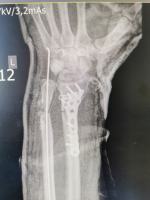

W wyniku pilnej interwencji chirurgicznej u 44-letniego Pacjenta w SP ZOZ w Kędzierzynie-Koźlu wykonano zespolenie struktur ręki prawie odciętej w lewym przedramieniu. Po przeprowadzonej 3 godzinnej trudnej operacji Pacjent zachował rękę. Nie było powikłań po zabiegu i po półtoratygodniowym pobycie w szpitalu został wypisany i wraca do zdrowia.

Późnym popołudniem w poniedziałek 19 lipca br. do naszego szpitala trafił 44-letni mężczyzna z prawie odciętą w przedramieniu lewą ręką (częściowa amputacja na poziomie 1/3 dystalnej przedramienia lewego). Rozległy uraz powstał w wyniku kontaktu z maszyną do mieszania betonu. Ze względu na zachowane ukrwienie kończyny (poprzez tętnicę łokciową) Pacjent nie został zakwalifikowany do leczenia przez zespół replantacyjny.

Z uwagi na rozległy uraz oraz inne okoliczności zdarzenia podjęliśmy natychmiastowe działania ratujące rękę Pacjenta. Zespół operacyjny pod kierunkiem dr Marcina Felsza dokonał zespolenia kości promieniowej (płytką LCP Hofer) oraz stabilizację złamania kości łokciowej (drutem Kirschnera). Połączono także ścięgna i pozostałe struktury ręki. Operacja trwała ok. 3 godzin.

- Pacjent urazu doznał w kontakcie z maszyną do produkcji betonu. Próbowaliśmy się skontaktować z oddziałami chirurgii ręki, ale one nie miały możliwości zaopatrzenia. Musieliśmy sobie poradzić sami. Przyjęliśmy Pacjenta do oddziału. Okazało się 4/5 obwodu zostało przecięte, po dokładniejszym zbadaniu była szansa że kończyna przeżyje. Zabieg wykonano w znieczuleniu ogólnym. Wykonaliśmy zabieg zespolenia kości i zeszyliśmy struktury miękkie, część ukrwienia została zachowana. Pacjent dobrze to zniósł, nie było zaburzeń ukrwienia. Nie było powikłań w okresie pooperacyjnym i Pacjent został wypisany do domu - powiedział dr Marcin Felsz - Kierownik Oddziału Urazowo-ortopedycznego.